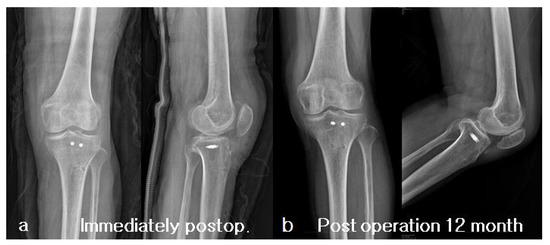

2. Case Presentation